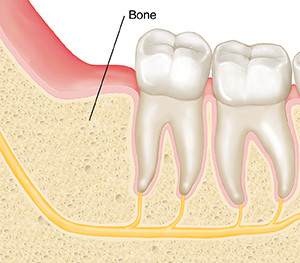

Healing after wisdom teeth removal usually takes a few months. First, a blood clot forms in the socket where the wisdom tooth was removed. This blood clot needs to stay in place to protect the bone and nerves. Within a day or two, the socket starts filling with repair tissue. This lays the foundation for new bone tissue to grow. When new bone tissue fills the socket, healing is complete.